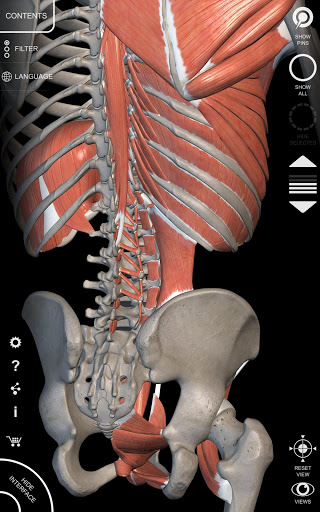

"Anatomy 3D Atlas" cho phép bạn nghiên cứu giải phẫu người theo cách dễ dàng và tương tác.

Thông qua giao diện đơn giản và trực quan, bạn có thể quan sát mọi cấu trúc giải phẫu từ mọi góc độ.

Các mô hình giải phẫu 3D đặc biệt chi tiết và có kết cấu lên đến độ phân giải 4k.

• Hệ thống cơ xương

• Tùy chọn ẩn hoặc cô lập một hoặc nhiều mô hình đã chọn

• Bộ lọc để ẩn hoặc hiển thị từng hệ thống

• Hình dung các cơ qua các lớp từ lớp nông đến lớp sâu nhất